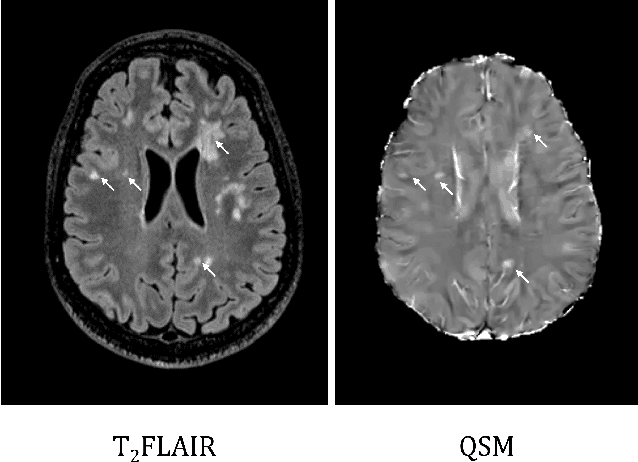

Abstract:Quantitative susceptibility maps from magnetic resonance images can provide both prognostic and diagnostic information in multiple sclerosis, a neurodegenerative disease characterized by the formation of lesions in white matter brain tissue. In particular, susceptibility maps provide adequate contrast to distinguish between "rim" lesions, surrounded by deposited paramagnetic iron, and "non-rim" lesion types. These paramagnetic rim lesions (PRLs) are an emerging biomarker in multiple sclerosis. Much effort has been devoted to both detection and segmentation of such lesions to monitor longitudinal change. As paramagnetic rim lesions are rare, addressing this problem requires confronting the class imbalance between rim and non-rim lesions. We produce synthetic quantitative susceptibility maps of paramagnetic rim lesions and show that inclusion of such synthetic data improves classifier performance and provide a multi-channel extension to generate accompanying contrasts and probabilistic segmentation maps. We exploit the projection capability of our trained generative network to demonstrate a novel denoising approach that allows us to train on ambiguous rim cases and substantially increase the minority class. We show that both synthetic lesion synthesis and our proposed rim lesion label denoising method best approximate the unseen rim lesion distribution and improve detection in a clinically interpretable manner. We release our code and generated data at https://github.com/agr78/PRLx-GAN upon publication.